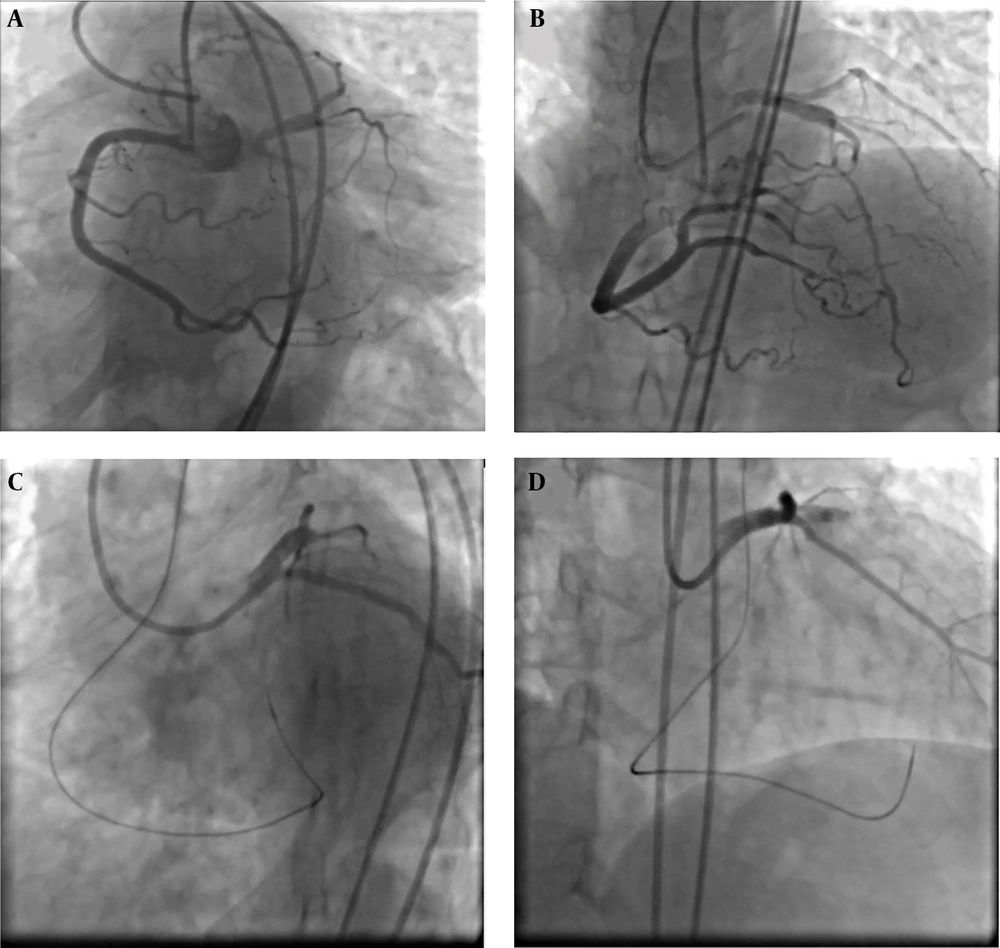

Lesion Preparation and Stenting: Sequential pre-dilatation was performed with a Ryurei 1.5×20 mm, Wilma NC 2.5×15 mm, and Accuforce 3.5×15 mm balloon. A Terumo Ultimaster 4.0×15 mm drug-eluting stent was deployed in the aorto-ostial LM segment. Final optimization and ostial flaring were achieved using a Conqueror 5.0×10 mm NC balloon (Figure 1).

Dual access injection showed left main chronic total occlusion (LM CTO) which was filled via retrograde approach through right coronary artery (A, B), then left main-left anterior descending artery (LM-LAD) was wired via conus branch of right coronary artery with black SION (C), then percutaneous coronary intervention (PCI) on LM-LAD was done (D).